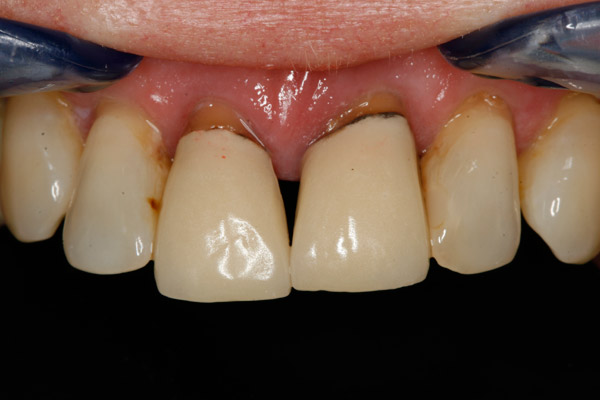

Thank you to our patients that have allowed us to show examples of our work

Have a look at just some of the many patient examples we have captured from BEFORE and AFTER their treatments and cosmetic surgeries.

From Whitening to Veneers, Fillings to Cosmetic Teeth Makeovers, here are some examples of the work that Dr. Dadabhai has provided to his patients to give them a more confident smile and a positive, pain free feeling.

Much of the work we carry out is to relieve pain and of course maintain the health of your teeth and gums, but many of our patients now ask for Cosmetic work to give them a more confident smile.

Cosmetic support has improved hugely over the last few years. Book a Consultation with Dr Dadabhai and he will prescribe a course of treatment to complete your perfect SMILE transformation.

Slide your computer mouse or finger (touch screens) over the image to view BEFORE and AFTER comparison.